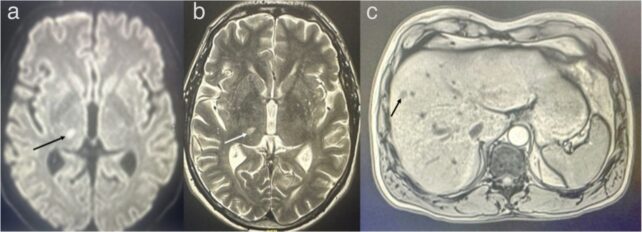

Hypertension is the most important risk factor for an ischemic stroke, and sure enough, a brain scan confirmed the presence of a blood clot in his brain.